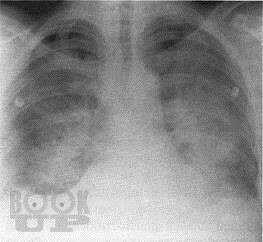

Бронхолегочные синдромы в пропедевтике внутренних болезней

Учебное пособие подготовлено в соответствии с ООП и учебным планом по дисциплине «Пропедевтика внутренних болезней» для обучающихся по специальности 31.05.01 «Лечебное дело». В учебном пособии изложены современные представления об основных синдромах при заболеваниях органов дыхательной системы, необходимых для обучающихся при изучении дисциплины «Пропедевтика внутренних болезней». Учебное пособие оснащено тестовыми заданиями и ситуационными задачами различной степени сложности для самоконтроля знаний с эталонами ответов. Учебное пособие предназначено для самостоятельной внеаудиторной работы обучающихся по специальности «Лечебное дело».